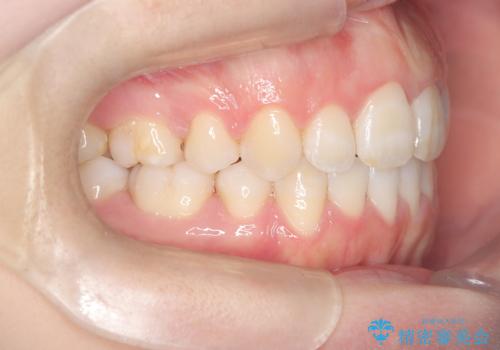

前歯のデコボコと開口を改善し、美しい口元へ

- 前歯のデコボコ(叢生)と、上下の歯が閉じない開口を主訴にご来院されました。精密な検査の結果、歯が並ぶスペースが不足しており、特に奥歯の咬み合わせが安定していないことが開口の原因と判明。患者様と相談し、上下左右の小臼歯を抜歯することでスペースを確保し、審美ワイヤー矯正で全体を整える治療計画を立案しました。これにより、見た目の改善だけでなく、機能的な咬み合わせも獲得することを目指します。

今回の矯正治療では、歯が並ぶスペースを確保するため、上下左右の小臼歯を抜歯しました。装置には目立ちにくい審美ワイヤーを使用し、見た目に配慮しながら治療を進めました。抜歯によってできたスペースを利用して歯を並べ、前歯のデコボコを解消。同時に、歯列全体を動かすことで、上下の歯がきちんと閉じる開口も改善しました。治療期間は約2年間。治療の結果、コンプレックスだった前歯のデコボコと開口が解消され、整った美しい歯並びと、しっかり咬める機能的な咬み合わせを獲得していただけました。